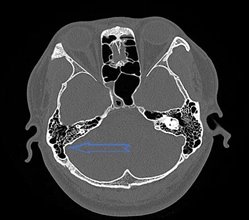

总之,耳朵里出现了类似心跳的声音时,千万不要掉以轻心。一定要及时就医,进行全面的检查和诊断,以便早期发现病因,采取有效的治疗措施,避免病情延误和加重。特别是乙状窦前位及颈静脉球高位,认识到它的影像特点,尤其是颞骨高分辨CT扫描通过多平面的重建图像,很容易精确诊断,清楚地了解乙状窦的形态,看看有没有憩室,憩室大小如何,局部骨质的状况,以及有没有合并颈静脉球高位,有助于帮助临床医生了解部分搏动性耳鸣患者的发病原因,采取有效的治疗手段。